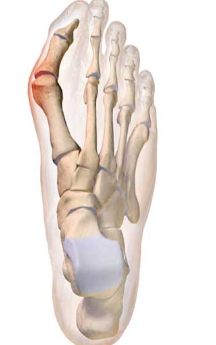

무지외반증("hallux valgus”)이란?

무지외반증은 발가락 통증을 일으킬 수 있는 특정한 상태입니다. 이는 발가락으로 통증을 유발할 수 있는 신경 주위의 조직이 두껍고 확장되는 경우 발생합니다. 이는 특히 세 번째와 네 번째 발가락 사이의 발의 앞부분에서 심한 불편함을 초래할 수 있습니다.